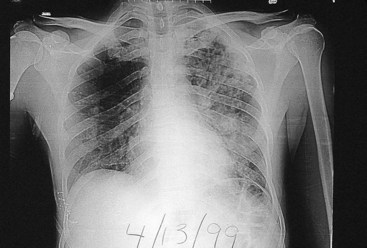

The clinical signs and symptoms of tuberculosis reflect the site of infection, with primary disease usually restricted to the lower respiratory tract. The disease is insidious at onset. Patients typically have nonspecific complaints of malaise, weight loss, cough, and night sweats. Sputum may be scant or bloody and purulent. Sputum production with hemoptysis is associated with tissue destruction (e.g., cavitary disease). The clinical diagnosis is supported by (1) radiographic evidence of pulmonary disease (Figure 25-5), (2) positive skin test reactivity, and (3) the laboratory detection of mycobacteria, either with microscopy or in cultures. One or both upper lobes of the lungs are usually involved in patients with active disease that includes pneumonitis or abscess formation and cavitation.

image

Figure 25-5 Pulmonary tuberculosis.